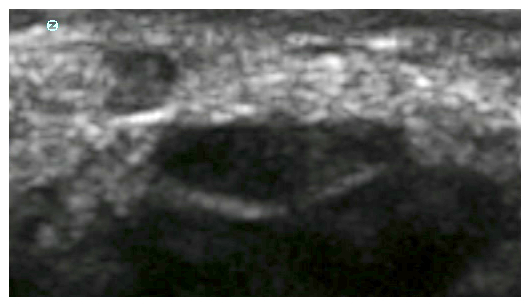

The carpal tunnel is a complicated 3-dimensional structure with a variety of different tissues within and around it. The scanners in routine use for this show you 2-dimensional 'slices' through this structure, the orientation depending on how you hold the ultrasound transducer. The first thing one appreciates when starting to look at it with an ultrasound scanner is that it is generally very easy to see the median nerve itself. In longitudinal sections, when the plane of the scan is aligned along the course of the nerve it generally appears as a dark (hypo-echoic) structure with a bright (hyper-echoic) line above and below it which is generated by the tough fibrous 'sheath' which surrounds the entire bundle of cells which constitute the nerve. Often this bright line is better seen at the side of the nerve nearer to the transducer.

Turn the ultrasound transducer through 90 degrees so that the plane of the scan is across the wrist and perpendicular to the course of the nerve and you then see the nerve as an irregularly shaped round/oval/triangular structure. Again the centre of the nerve is dark (hypoechoic) and the nerve sheath appears as a bright line surrounding it. It is often possible to see the entire circumference of sheath around the nerve but not always.

The nerve can be distinguished from the surrounding tendons by the way the tendons move with finger movement and by the fact that the tendons change markedly from dark to light in the ultrasound image with slight tilting of the transducer - a property known as anisotropy. The shape of the nerve in transverse section varies widely from individual to individual:-